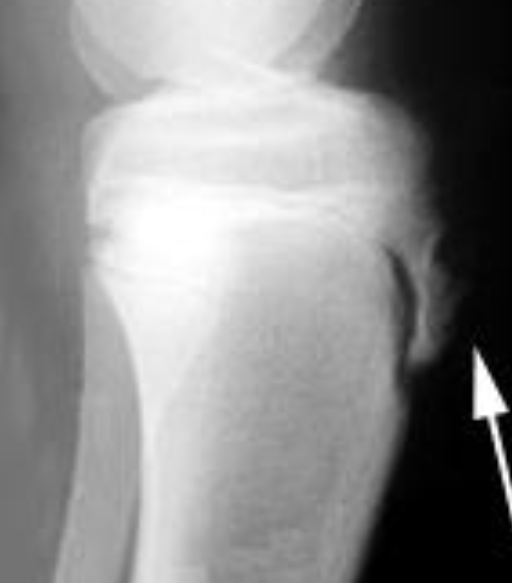

Los extremos del hueso aparecen ensanchados (en pata de elefante) En este caso el principal problema es la falta de estabilidad. El hueso tiene capacidad para consolidar, pero los micromovimientos en el foco impiden que la consolidación se complete. Requieren síntesis rígidas a compresión como tratatamiento de elección (enclavado intramedular